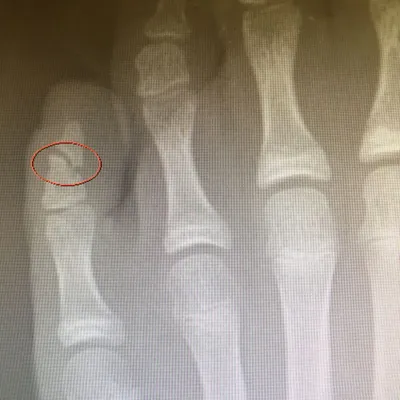

Below is an x-ray image of an extra-articular fracture of the proximal phalanx of the hallux (great toe) of a child. the fracture line does not enter the joint.